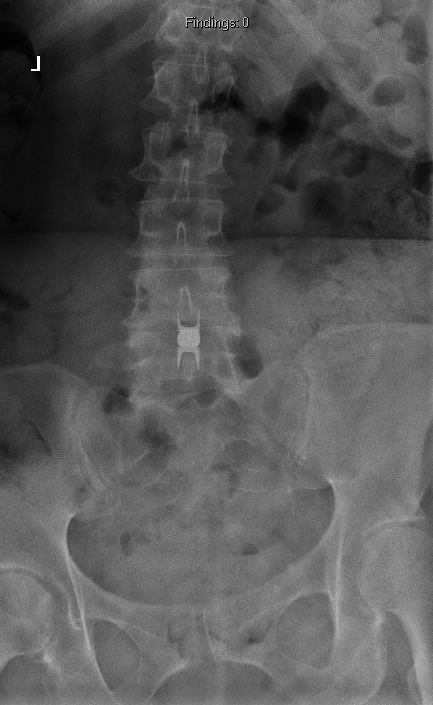

From robotics and AI-driven surgical planning to virtual modeling and custom implants, I’ve embraced a combination of tools that allow me to create tailored surgical plans for my patients—particularly those with scoliosis and spinal deformities.

What sets my approach apart is the seamless integration of these advanced technologies to ensure unparalleled accuracy and better outcomes for each patient.